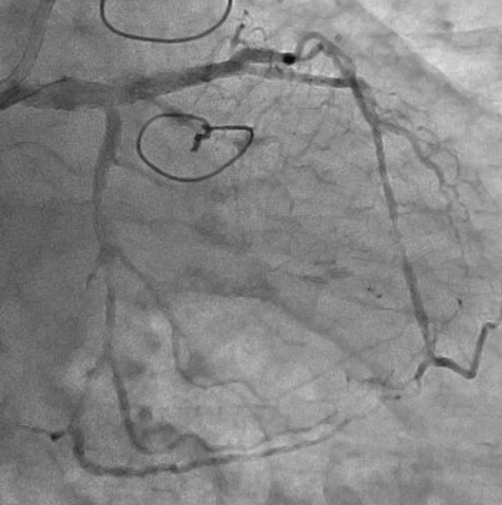

The left internal thoracic artery–left anterior descending artery (LAD) graft was completely occluded, and the native left coronary artery (LCA) was also occluded at the ostium of the left main trunk (LMT). The right coronary artery demonstrated no significant stenosis. From a right ventricular branch, non-interventional epicardial channels opacified the separated LAD and left circumflex artery. The occlusion length from the ostium of the long LMT to the bifurcation, was approximately 15 mm.

First, percutaneous coronary intervention (PCI) was performed toward the left anterior descending artery (LAD). The initial antegrade wire deviated from the true lumen; therefore, parallel wire technique was employed to achieve successful crossing. To avoid jailing the left circumflex artery (LCX) ostium, the stent was deployed precisely at the LAD ostium, and the left main trunk (LMT) was dilated using a 4.0-mm cutting balloon. One month later, intervention toward the LCX was undertaken. Intravascular ultrasound (IVUS) performed from the LAD confirmed achronic total occlusion (CTO) entry with a markedly thick plaque covering the LCX ostium. Although the lesion was accurately marked, penetration with a high-penetration guidewire was unsuccessful. Even with the balloon screen technique using a CP 8-20, wire penetration remained unsuccessful. Therefore, plaque debulking was selected to expose the CTO entry. Directional coronary atherectomy (DCA) was performed, and follow-up IVUS demonstrated significant plaquethinning compared with baseline. Subsequently, the CP 8-20 wire advanced smoothly, enabling successful wire crossing. The procedure was completed usinga mini-crush stenting strategy.

Aorto-ostial CTO of the LMT is extremely rare, accounting for approximately 0.1% of all CTOs. In this case, the lesion was particularly unique due to its unprotected LMT, absence of retrogradeoption, and completely separated distal bifurcation. In a bifurcation with separated branches, successful wire passage into one branch inevitably resultsin ¡°short-cut¡± the entry of the other branch. In this case, cutting angioplasty could not modify the cap; therefore, directional coronary atherectomy (DCA) was employed. Although DCA is currently approved only in Japan, the essential concept is targeted plaque modification at the entry, which may also be achieved with other atherectomy modalities.